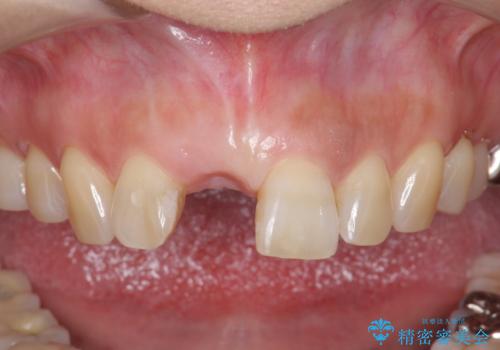

- 前歯を外傷により失い、審美性の改善を求めて来院されました。

横の歯を削る必要のあるブリッジ治療、着脱の必要な入れ歯に強い抵抗があったためインプラント治療を計画します。

審美的・機能的に良好な位置に埋入するには、骨量が十分ではなかったため骨の造成を併用したインプラント埋入外科手術を行います。